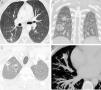

Presentamos el caso de un paciente de 30 años diagnosticado en 2011 de un síndrome de Ehlers-Danlos vascular (también llamado síndrome de Ehlers-Danlos tipo IV) que presentó varios episodios de neumotórax bilateral en los últimos 2 años. Aunque las complicaciones más importantes de este paciente han estado relacionadas con la formación y la rotura espontánea de aneurismas en múltiples arterias (carótida, renal, esplénica, vertebral…), desde 2013 viene observándose la aparición radiológica incidental de nódulos pulmonares con una presentación muy variable: nódulos sólidos (fig. 1A), nódulos subsólidos (fig. 1B), nódulos cavitados (fig. 1C), y nódulos con calcificaciones en su interior (fig. 1D).

A) Imagen axial de la TC de tórax (ventana de parénquima pulmonar) realizada en 2013 en la que se observa un nódulo sólido en lóbulo inferior derecho (flecha). B) Imagen coronal de la TC de tórax (ventana de parénquima pulmonar) realizada en 2014 en la que visualiza la aparición de 2 nódulos en pulmón derecho: uno sólido (flecha) y otro subsólido de atenuación predominante en vidrio deslustrado con un pequeño centro sólido (asterisco). C) Imagen axial de la TC de tórax (ventana de parénquima pulmonar) realizada en 2016 en la que se demuestra la aparición de 2 nódulos pulmonares cavitados en vértice pulmonar derecho (flechas). Nótese que el nódulo más lateral presenta una cavitación excéntrica con morfología en semiluna. D) Imagen axial de la TC de tórax (ventana de mediastino) realizada en 2017 en la que se observa la aparición de una calcificación lineal (flecha) en el interior de un nódulo sólido en el lóbulo medio.